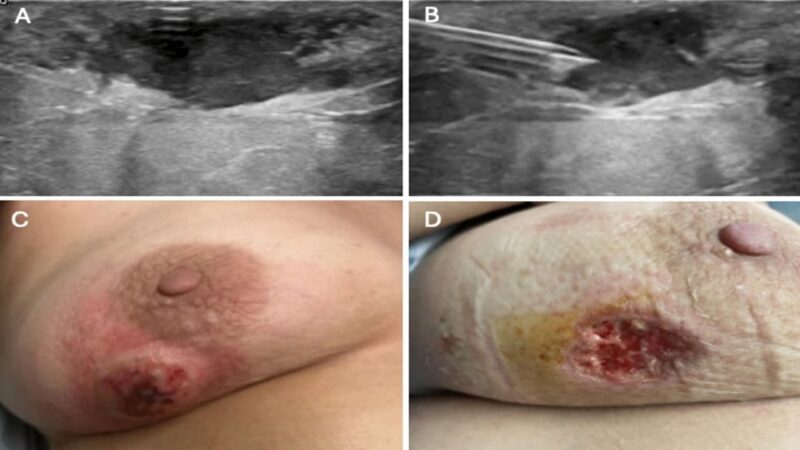

Khám phá lâm sàng

Bác sĩ quan sát và khoanh vùng tổn thương để xác định có mủ hay không.

T lâm

Siêu âm

CT

Phương pháp này giúp xác định vị trí và khả năng lây lan nhiễm độc, đặc biệt với áp dụng chiều sâu.